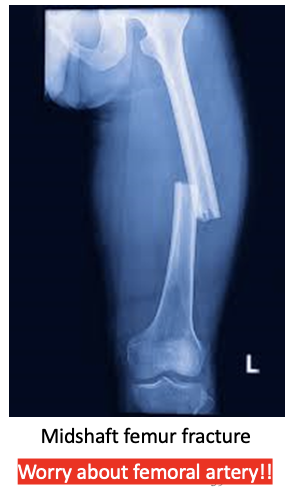

what is a Femoral Shaft Fractures

(specific)

Fracture of the femoral shaft -

between 5cm distal to the lesser trochanter and 5cm proximal to the adductor tubercle

major concern with femural shaft fx’s?

BLEEDING OUT!! many pts will need blood transfusions!!

what is the major blood supply of the femur?

deep (profunda) femoral artery

Treatment of Femoral Shaft Fractures

screw ‘em

Intramedullary (IM) nailing

External fixation

Plate fixation

—> operative stabilization